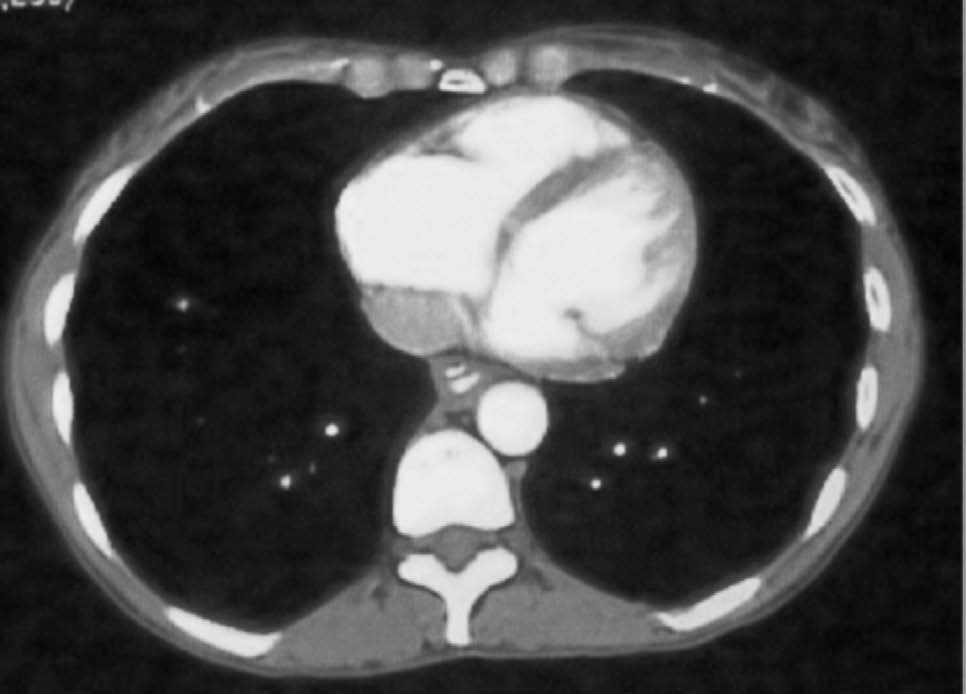

Fig. 3. Tomografía computarizada con contraste oral e intravenoso. Signo doble luz.

Mujer de 42 años, que acude al servicio de urgencias al presentar un cuadro de dolor torácico retroesternal, no irradiado, de unas 12 h de evolución, acompañado de disfagia, odinofagia, sialorrea y regurgitación de contenido hemático-purulento, junto con fiebre de 39 oC. Entre los antecedentes personales destacaban episodios de disfagia ocasional desde la infancia, y tras múltiples pruebas complementarias (estudio baritado esofágico, endoscopia digestiva alta y manometría) se diagnosticó un trastorno motor esofágico inespecífico. Durante el ingreso se le realizaron diferentes pruebas: a) estudio baritado esofágico sin apreciar lesiones; b) endoscopia digestiva alta (figs. 1 y 2) con sedación profunda, donde se visualiza una estenosis parcial de la luz esofágica por compresión extrínseca a unos 20 cm de arcada dentaria, precedida de una laceración mucosa profunda en la pared esofágica con tractos fibrosos, del que rezuma sangre fresca en escasa cuantía; c) tomografía computarizada (TC) helicoidal torácica con y sin contraste intravenoso (fig. 3), donde se observa una formación tubular, que sigue casi todo el trayecto del esófago, con una cápsula bien definida que capta el contraste intensamente y que parece localizarse en el interior de la pared esofágica, con burbujas aéreas en su porción proximal, compatible con absceso esofágico intramural o quiste de duplicación esofágico complicado.

El diagnóstico se hace mediante el estudio esofágico con contraste hidrosoluble (signo de la doble luz), endoscopia digestiva alta o TC. El esofagograma es menos traumático que la endoscopia y nos determinará la indemnidad del esófago. La endoscopia no es especialmente peligrosa si se hace con cuidado, nos aportará el diagnóstico definitivo y puede ser útil para el seguimiento y tratamiento de esta enfermedad8. La TC puede ser útil para el diagnóstico diferencial con otras enfermedades con clínica similar, como el aneurisma disecante de aorta o la perforación esofágica, que requieren un tratamiento quirúrgico urgente.